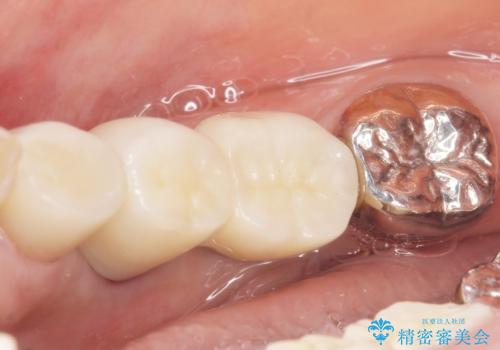

奥歯でしっかり咬むことができるようになり、大変喜んで頂けました。

クラウンの種類:オールセラミッククラウン ベレッツァ